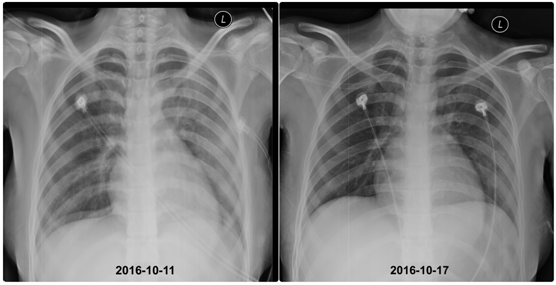

第4天,复查胸片,双肺部渗出影明显吸收;

第9天,肺部CT提示双肺高密度影显著吸收,血红蛋白逐渐上升至70g/L,血氧分压正常。